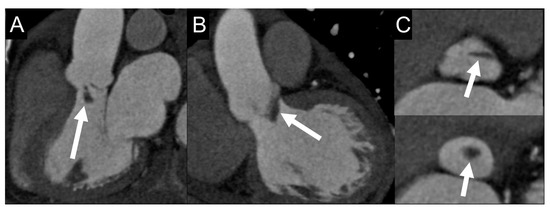

4.3. Role of CCTA in Diagnosing IE and Local Complications

- Kim, I.C.; Chang, S.; Hong, G.R.; Lee, S.H.; Lee, S.; Ha, J.W.; Chang, B.C.; Kim, Y.J.; Shim, C.Y. Comparison of cardiac computed tomography with transesophageal echocardiography for identifying vegetation and intracardiac complications in patients with infective endocarditis in the era of 3-dimensional images. Circ. Cardiovasc. Imaging 2018, 11, e006986. [Google Scholar] [CrossRef]

- Feuchtner, G.M.; Stolzmann, P.; Dichtl, W.; Schertler, T.; Bonatti, J.; Scheffel, H.; Mueller, S.; Plass, A.; Mueller, L.; Bartel, T.; et al. Multislice Computed Tomography in Infective Endocarditis. J. Am. Coll. Cardiol. 2009, 53, 436–444. [Google Scholar] [CrossRef] [PubMed]

- Entrikin, D.W.; Gupta, P.; Kon, N.D.; Carr, J.J. Imaging of infective endocarditis with cardiac CT angiography. J. Cardiovasc. Comput. Tomogr. 2012, 6, 399–405. [Google Scholar] [CrossRef]